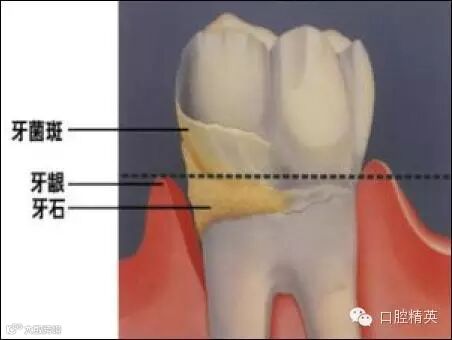

牙结石是如何附着在牙龈周围的